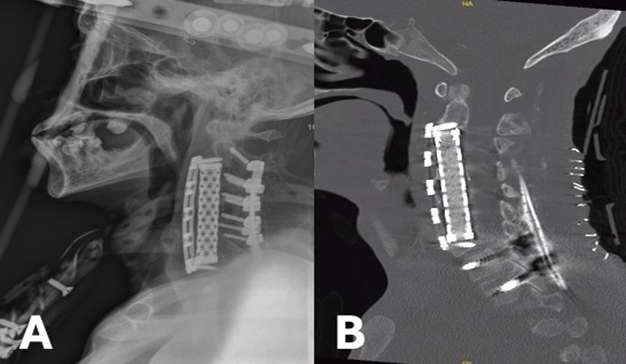

52-year-old male with past medical history significant for diabetes mellitus (DM), end-stage renal disease (ESRD), heart failure with preserved ejection fraction (HFpEF), deep venous thrombus (DVT) with inferior vena cava (IVC) filter presented to the hospital with a chief complaint of bilateral upper extremity (BUE) deltoid weakness with associated paresthesias and bowel incontinence for six days. Past surgical history significant for revision C3-C5 ACCF and C2-C5 posterior cervical fixation one month prior for methicillin-resistant staphylococcus aureus (MRSA) osteomyelitis. Cervical x-ray (XR) and computed tomography (CT) Cervical Spine discovered subsidence of the corpectomy hardware and cervical kyphosis resulting in retropulsion of the bone and hardware (Figure 1A and B). MRI Cervical Spine confirmed severe canal stenosis and draping of the spinal cord over the retropulsed fragment (Figure 1C). The patient was placed in cervical traction using Gardner-Wells tongs, which improved the cervical kyphosis and the patient’s neurologic exam. On hospital day (HD) one, the patient was taken to the operating room for revision corpectomy to include C3-C6 and extension of the posterior cervical construct. Post-operatively, the patient regained full strength and sensation. CT scan completed on post-operative day (POD) three demonstrated early subsidence and thus the patient was placed in a halo brace (Figure 2). Unfortunately, patient’s hospital course was complicated by worsening gastrointestinal bleeding and ultimately septic shock. He passed away one month following surgery.

Figure 2: Post-operative lateral XR showing improved cervical alignment and the halo brace (A). Post-operative sagittal CT Cervical Spine without Contrast demonstrating proper position of anterior and posterior hardware (B).